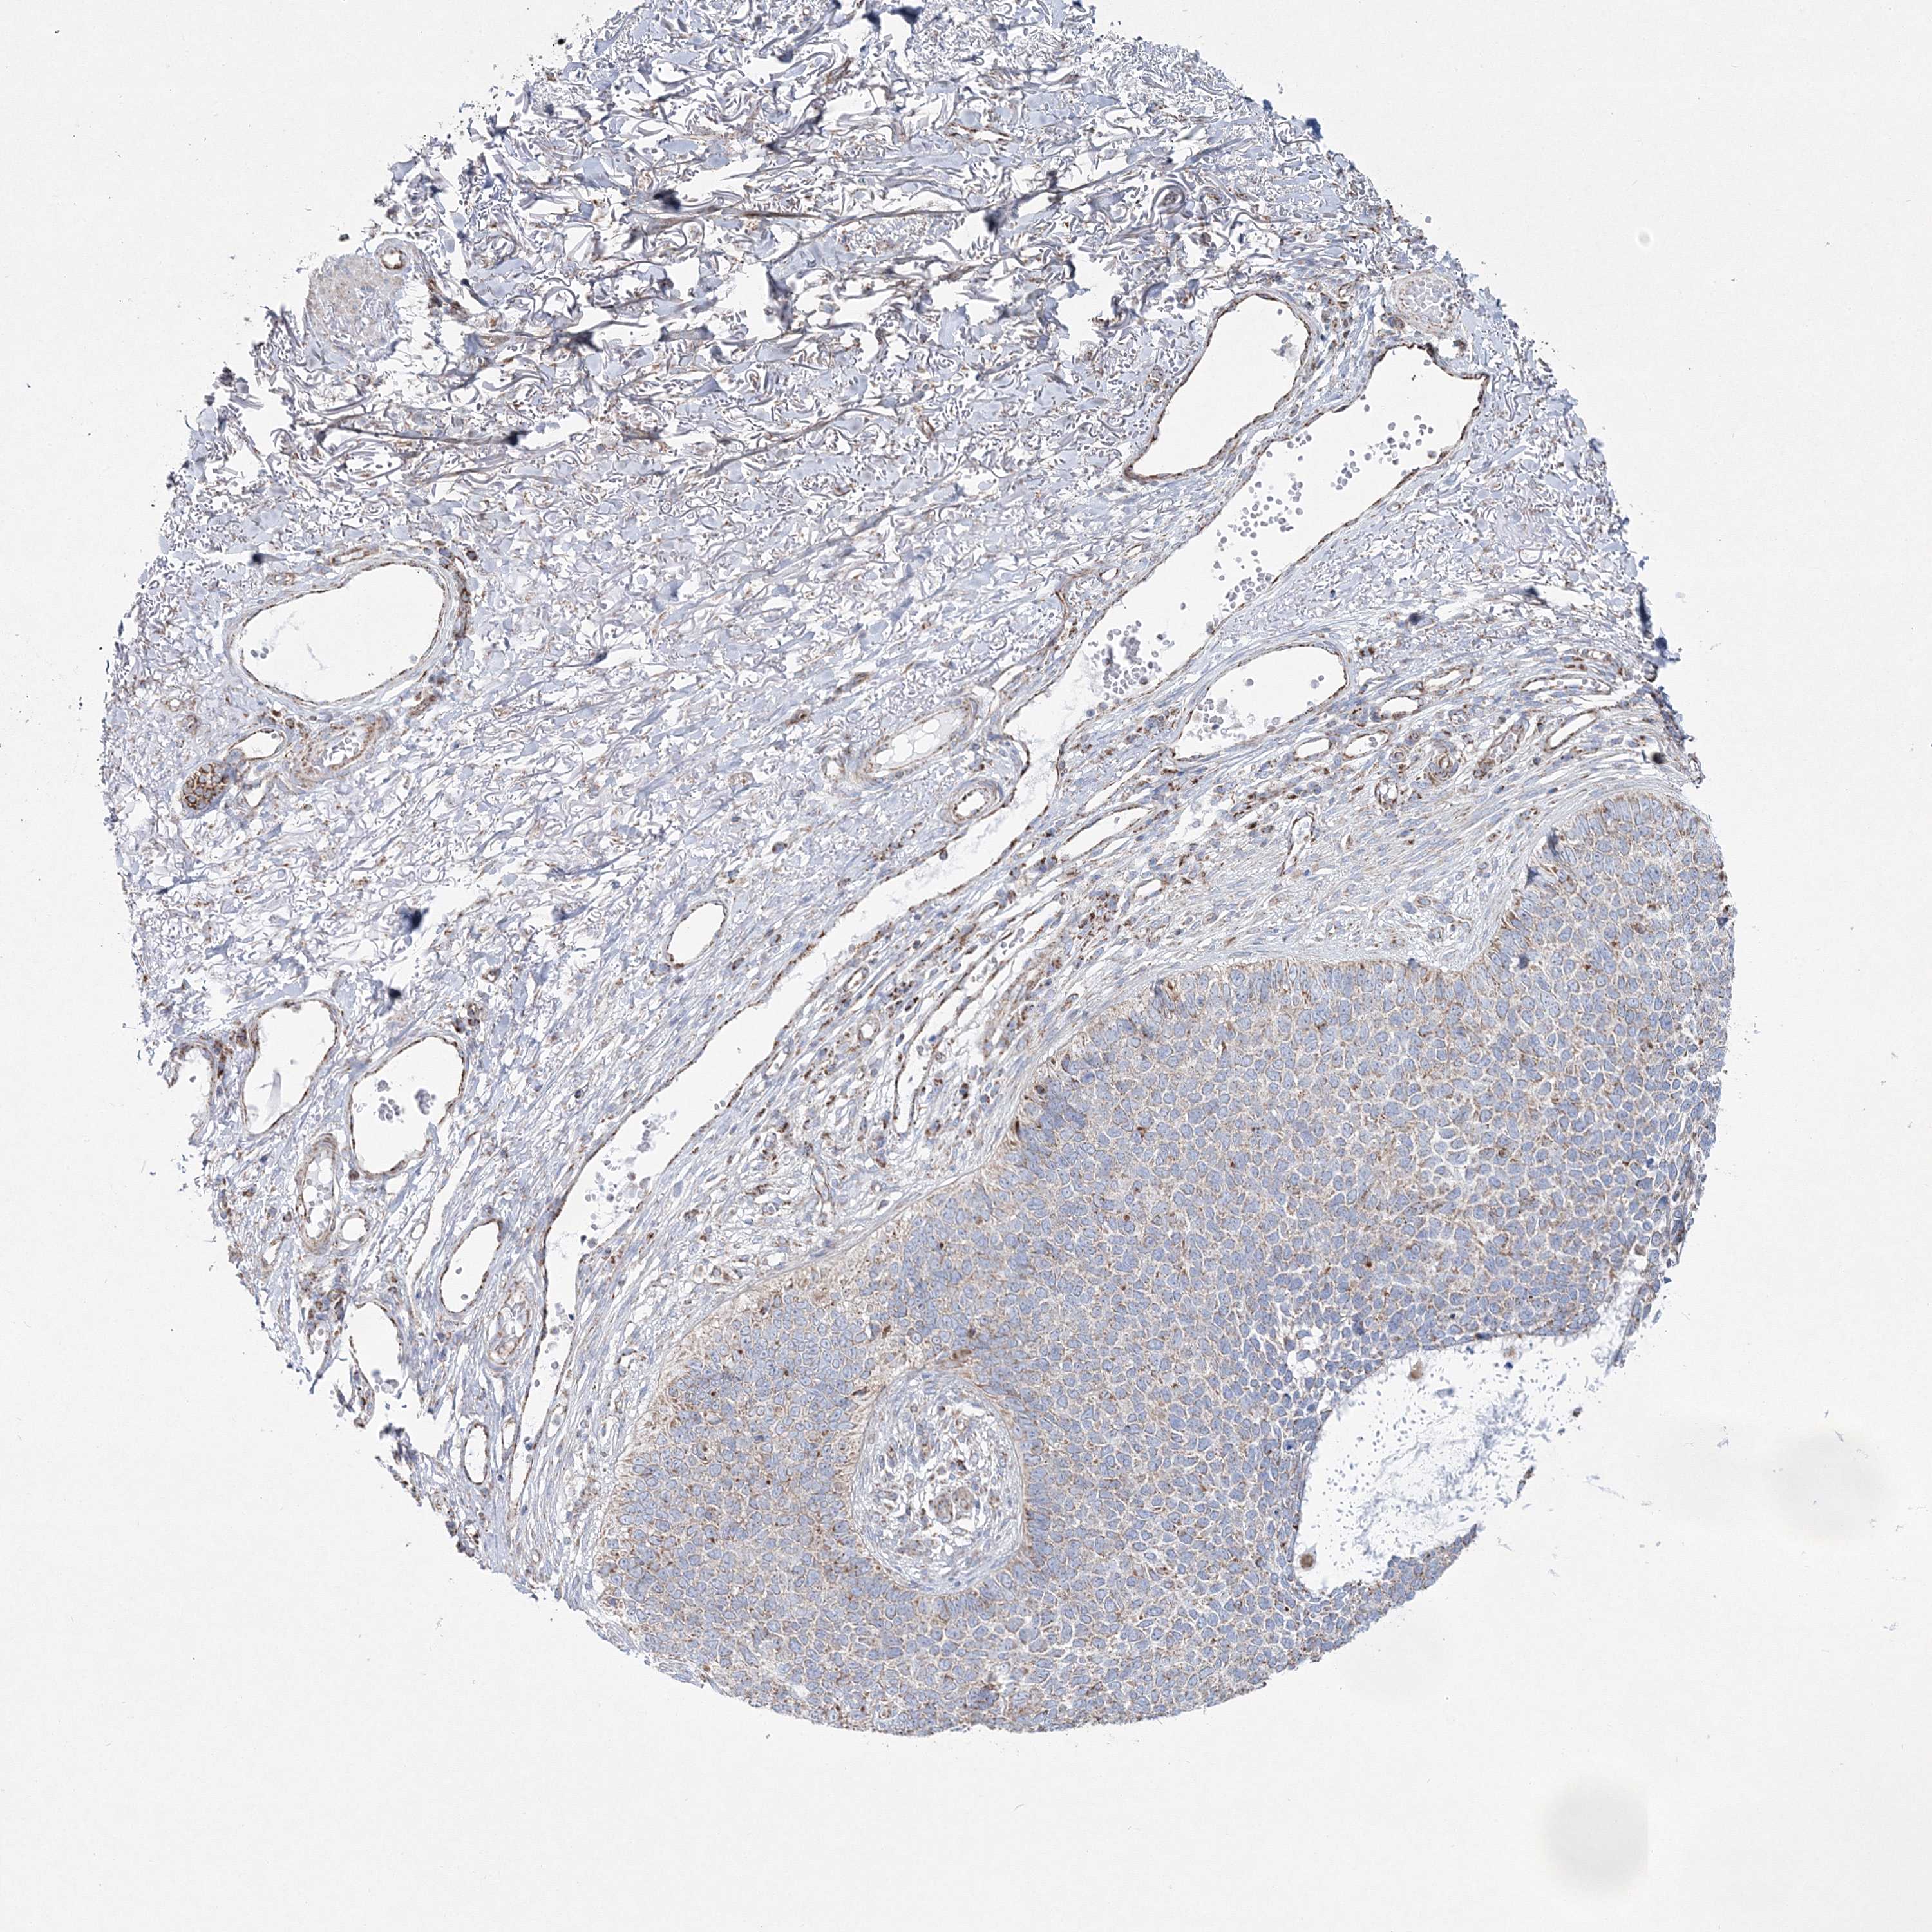

Basal cell and squamous cell cancer

SKIN CANCER - Protein expressioni

A mouse-over function shows sample information and annotation data. Click on an image to view it in a full screen mode. Samples can be filtered based on level of antibody staining by selecting one or several of the following categories: high, medium, low and not detected. The assay and annotation is described here.

Antibody stainingi

Antibody staining in the annotated cell types in the current human tissue is reported as not detected, low, medium, or high, based on conventional immunohistochemistry profiling in selected tissues. This score is based on the combination of the staining intensity and fraction of stained cells.

Each image is clickable and will lead to virtual microscopy that enables deeper exploration of all samples and also displays staining intensity scores, fraction scores and subcellular localization as well as patient and tissue information for each sample.

Antibody HPA036540

Antibody HPA036541

Staining

High

Medium

Low

Not detected

Intensity

Strong

Moderate

Weak

Negative

Quantity

>75%

75%-25%

<25%

None

Location

Nuclear

Cytoplasmic/membranous

Cytoplasmic/membranous,nuclear

Basal cell carcinoma

Squamous cell carcinoma, NOS

Squamous cell carcinoma, metastatic, NOS